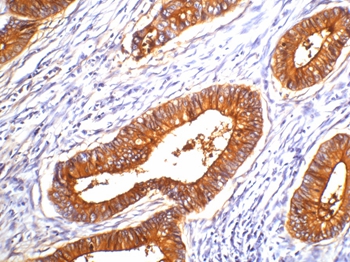

分类: 科研抗体货号: P42984别名: CEA;Pregnancy-specific glycoprotein 2; PS-beta-E; PS-beta-G-2; PSBG-2; PSBG2; PSG1; PSG2; PSGGB应用: IHC,IF反应种属: Human